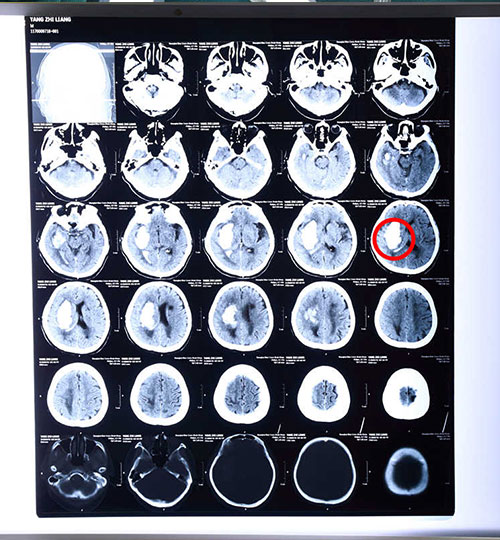

病人術(shù)前顱腦CT影像資料,紅圈內(nèi)白色陰影區(qū)為出血部位

據(jù)了解,腦出血是一種十分兇險(xiǎn)的病癥,一般大腦出血量達(dá)30毫升,若救治不及時(shí)便可能出現(xiàn)生命危險(xiǎn),而老人74毫升的出血量在臨床上即使救治及時(shí),其死亡率也可高達(dá)90%及以上,再加上老人年事高,且目前已呈嗜睡狀態(tài),狀態(tài)較差,治療也更有難度。